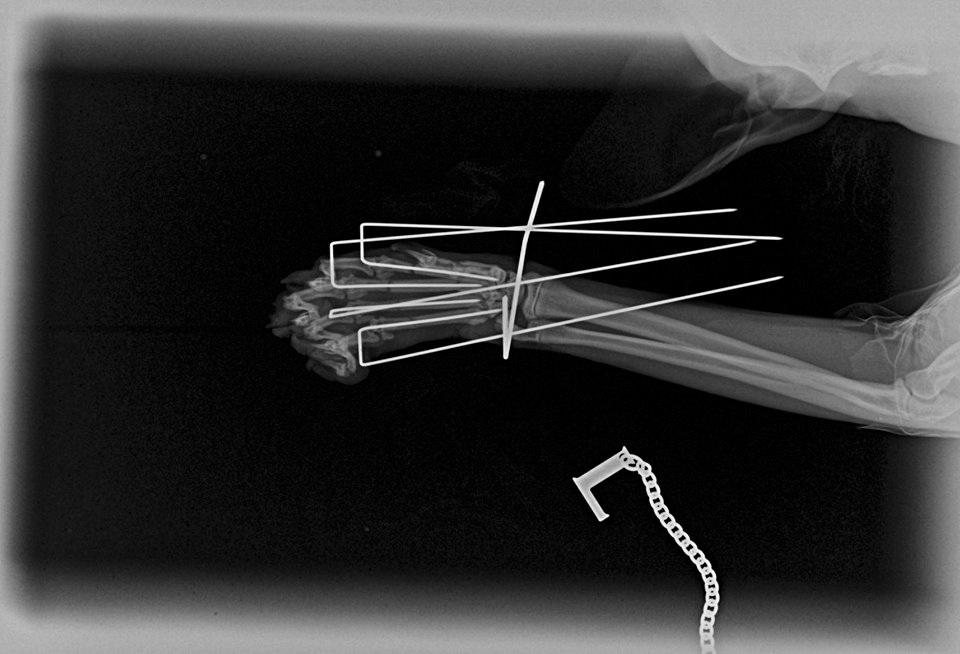

Tento černý kocourek spadl z 2. patra a zlomil si záprstí na jedné přední končetině. Konkrétně se jedná o sériovou frakturu všech metacarpálních kostí. Aby mohl zase běhat, bez operace se to neobešlo. Použili jsme externí skeletní fixaci tzv. „spider frame“, který poprvé použil Dr. Fitzpatrick, UK.